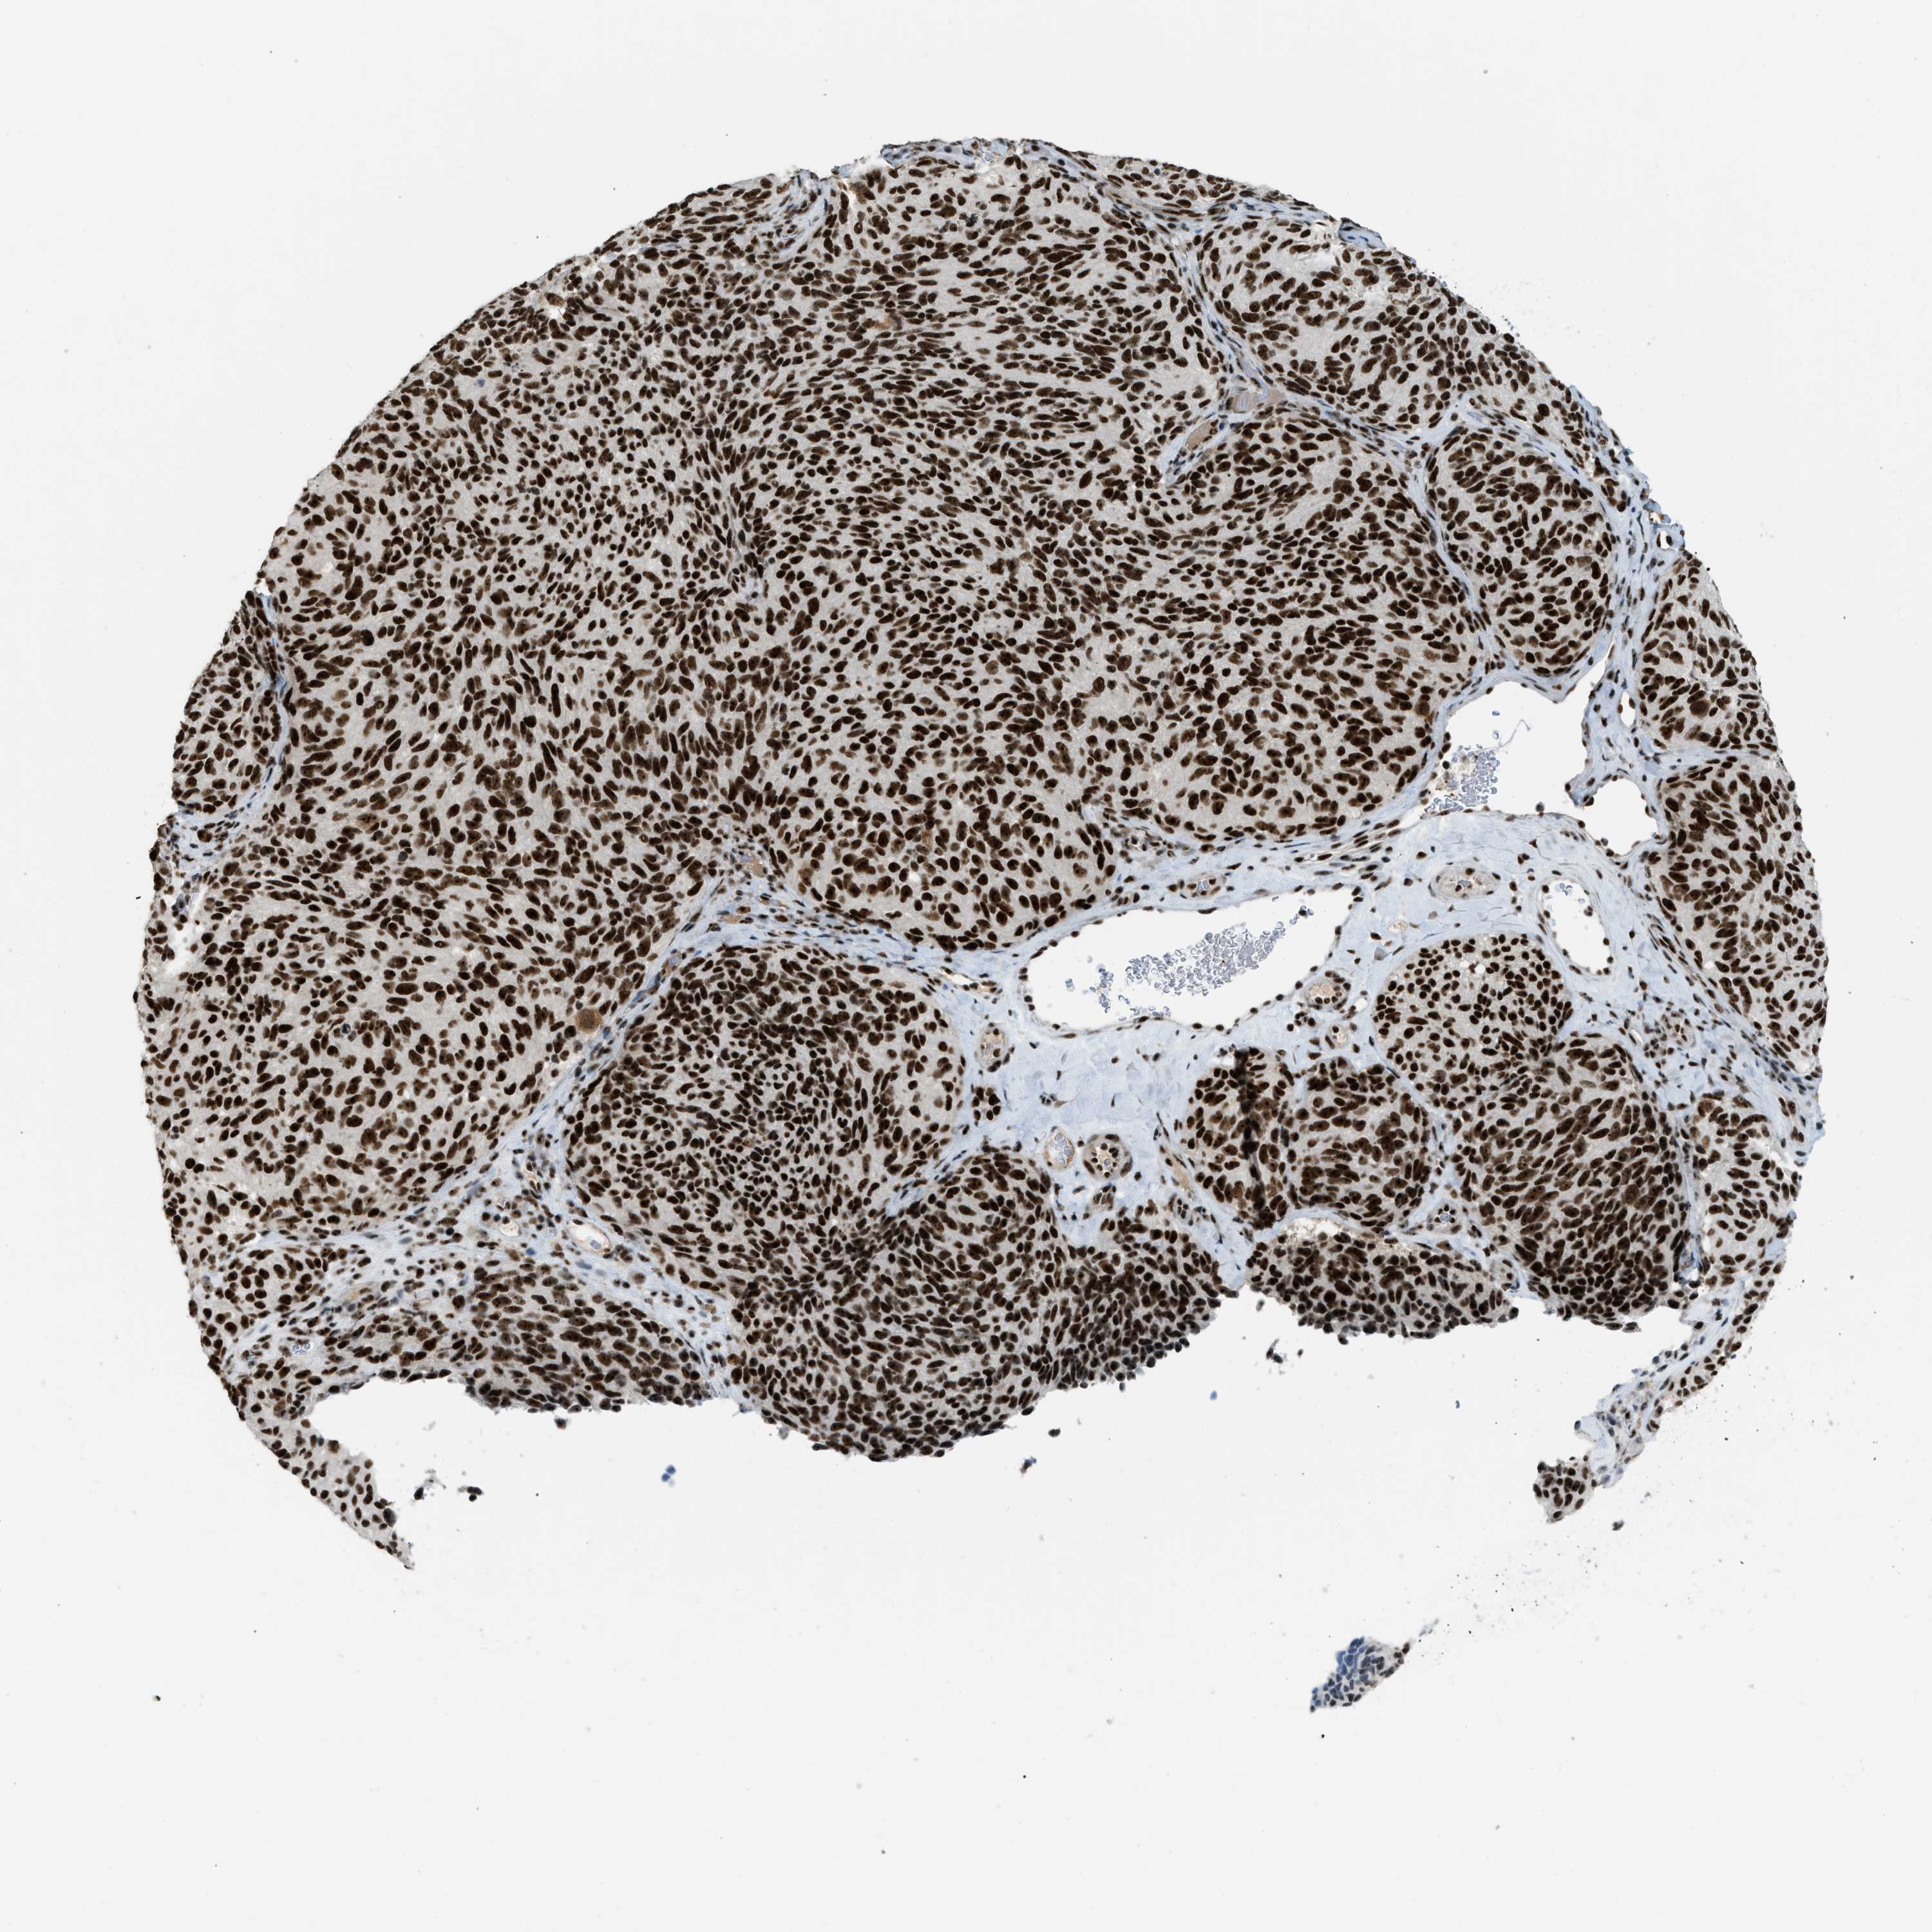

MELANOMA - Protein expressioni

A mouse-over function shows sample information and annotation data. Click on an image to view it in a full screen mode. Samples can be filtered based on level of antibody staining by selecting one or several of the following categories: high, medium, low and not detected. The assay and annotation is described here.

Note that samples used for immunohistochemistry by the Human Protein Atlas do not correspond to samples in the TCGA dataset.

Antibody stainingi

Antibody staining in the annotated cell types in the current human tissue is reported as not detected, low, medium, or high, based on conventional immunohistochemistry profiling in selected tissues. This score is based on the combination of the staining intensity and fraction of stained cells.

Each image is clickable and will lead to virtual microscopy that enables deeper exploration of all samples and also displays staining intensity scores, fraction scores and subcellular localization as well as patient and tissue information for each sample.

Antibody HPA018334

Staining

High

Medium

Low

Not detected

Intensity

Strong

Moderate

Weak

Negative

Quantity

>75%

75%-25%

<25%

None

Location

Nuclear

Cytoplasmic/membranous

Cytoplasmic/membranous,nuclear

Malignant melanoma, Metastatic site